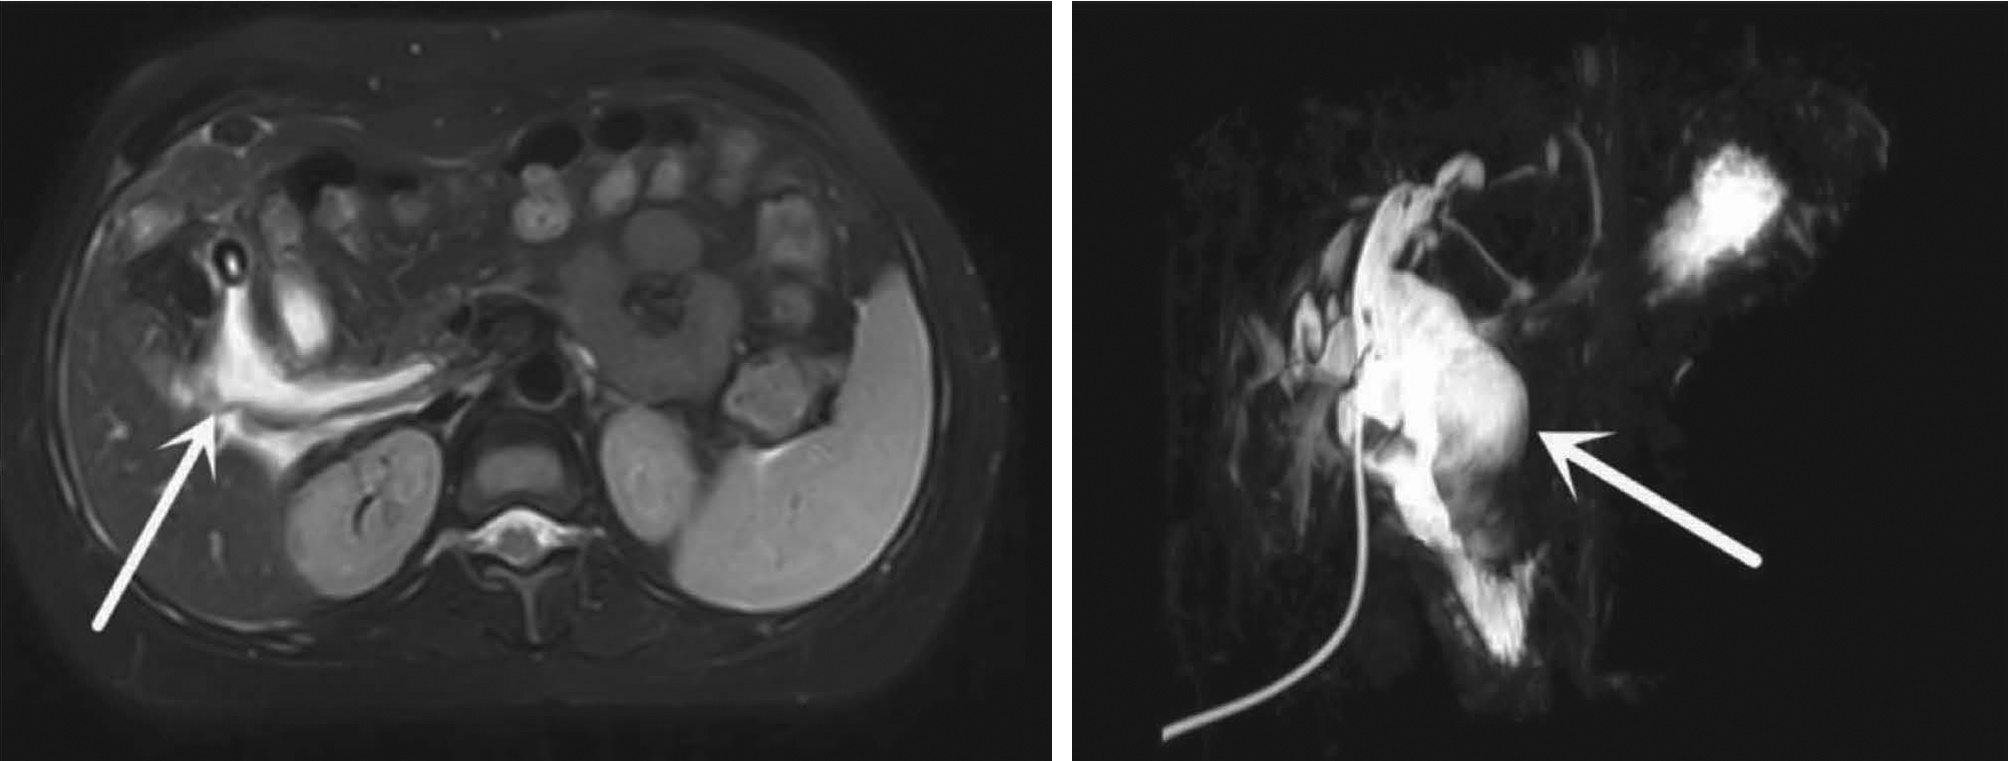

Spontaneous rupture of biliary dilatation with cancer: A case report

Xiaotong QIU, Zhengqi WU, Yushi CAO, Xuxiang XIA, Guoyue LYU

2022, 38(5): 1129-1130. DOI: 10.3969/j.issn.1001-5256.2022.05.031

Abstract(907) HTML (321) PDF (2537KB)(30)

Abstract: